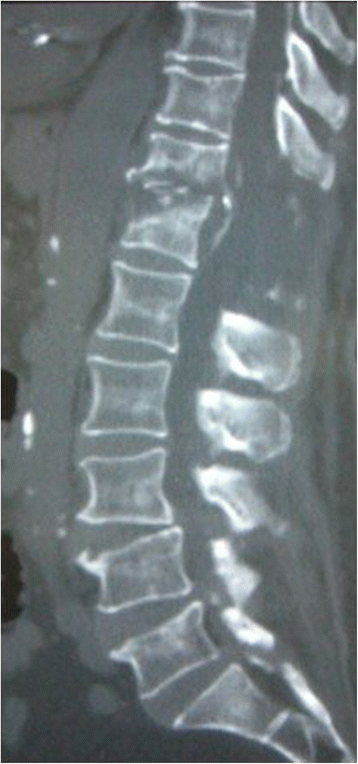

Admission laboratory values included a white blood cell count (WBC) of 18,800 per mm3, her hemoglobin was 9.4g/dL, and her hematocrit was 30%. Her Westergren erythrocyte sedimentation rate was 80mm/hour, and C-reactive protein (CRP) was 30.02mg/dL. Initial radiographic examination of her lumbar spine at admission showed only spondylotic change. A computed tomography (CT) scan showed soft tissue swelling anterolaterally at intervertebral disc level T11/12 and a gas-containing epidural abscess that compressed her spinal cord (Figure 1). Magnetic resonance imaging showed involvement of the T11/12 disc space and adjacent vertebral body with decreased signal intensity on T1-weighted images and increased signal intensity on T2-weighted images with a gas-containing epidural abscess (Figure 2).

Postoperatively, she experienced some sensory and motor return in her legs, but back pain and left chest pain in the sitting position continued. A CT scan 6 weeks after the operation showed T12 vertebral bone destruction (Figure 3); her WBC count and CRP were 8800 per mm3 and 0.26mg/dL, respectively. She went on to have fusion surgery with instrumentation and subsequently experienced complete relief of her pain. She was discharged 2 months later, at which time she was able to walk with a cane. Examination 18 months after surgery showed normal gait without a cane. Plain radiograph at 18 months after operation showed complete union between the T11 and T12 vertebral bodies (Figure 4).